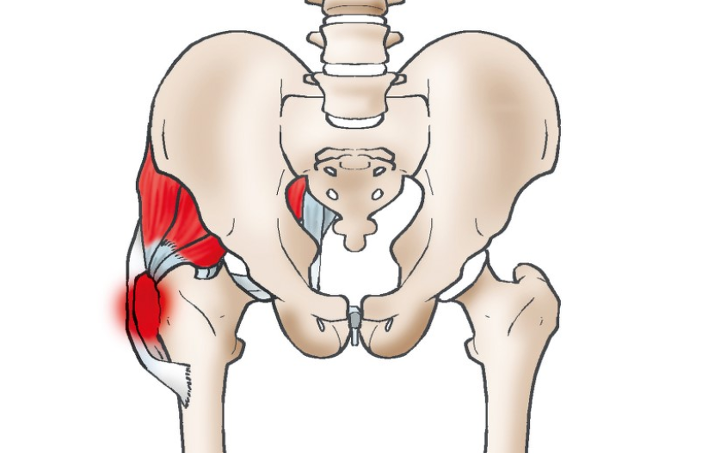

고관절은 엉덩이관절이라고도 불리우며, 보통 알고있는 골반위치에 있고, 공처럼 둥글게 생긴 대퇴골두가 글러브가 감싼듯한 모양으로 비구에 맞물려 있어요.

이렇듯 고관절은 오목하게 들어간 비구와 둥근 공모양의 대퇴골두로 이루어져 있으며 골반과 다리를 이어주는 우리 몸의 핵심 관절인데요. 그리고 고관절은 골반을 통해 전달되는 체중을 지탱해주고 걷기와 달리기같은 다리 운동들을 가능하게 해주는 관절이기도 해요.

고관절 통증 증상 - 고관절 충돌 증후군

뼈가 과도하게 튀어나와 고관절 충돌이 발생해요. 비구와 대퇴경부가 선천적 또는 후천적으로 커져 과도한 스트레칭이나 운동으로 충돌하며 고관절 통증 증상을 유발해요.

고관절 충돌 증후군으로 인해 고관절 통증 증상이 악화되면 비구순의 파열이 일어나고 관절 연골을 손상시켜요. 심하게되면 퇴행성 고관절염에 이를 수 있어요.